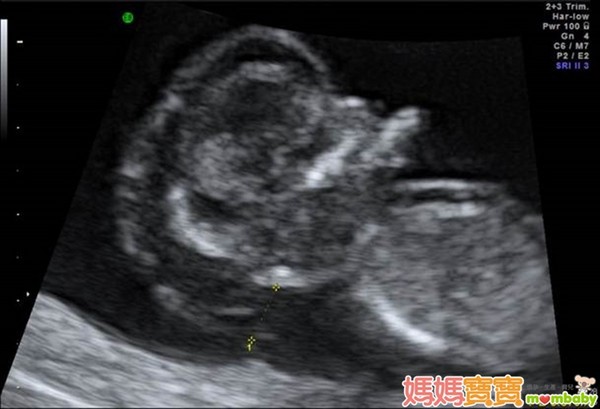

利用高解析度的超音波來檢查胎兒頸部透明帶厚度,以確認胎兒是否具備染色體或構造異常等疑慮,進而接受更進一步的評估,正是這個產檢項目的宗旨。

頸部透明帶的測量部位,為胎兒頸椎表皮與表皮底下軟組織的間隙,之所以會發展這樣的篩檢方式,是因為藉由以往的臨床經驗中逐漸得知,染色體與器官構造異常的胎兒,頸部透明帶似乎皆有變厚的傾向,例如唐氏症、透纳氏症候群、先天性心臟病等,這些疾病往往合併胎兒膠原組織組成改變,或淋巴及心血管循環出現異常,進而導致頸部透明帶變得較厚;因此,醫界便開始利用這個現象來回推檢測,觀察頸部透明帶較厚的胎兒是否有較高機率發生異狀,才會演變為現今的胎兒頸部透明帶篩檢。

頸部透明帶的檢查週數為懷孕第11週~第13週又6天之間,有些準媽媽可能會以月經週期來推算懷孕週數,但如果忘了最後一次的月經日期或平常月經不規則的孕婦,醫師會利用超音波來測量胎兒的頭臀徑(頭到臀部的長度,也就是胎兒坐姿高度),若頭臀徑介於36~84公厘之間,也達到適合檢查頸部透明帶的標準。